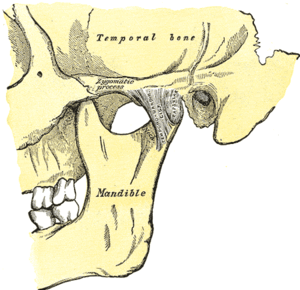

Temporomandibular joints

The temporomandibular joints are the dual articulation of the mandible with the skull. Each TMJ is classed as a "ginglymoarthrodial" joint since it is both a ginglymus (hinging joint) and an arthrodial (sliding) joint,[40] and involves the condylar process of the mandible below, and the articular fossa (or glenoid fossa) of the temporal bone above. Between these articular surfaces is the articular disc (or meniscus), which is a biconcave, transversely oval disc composed of dense fibrous connective tissue. Each TMJ is covered by a fibrous capsule. There are tight fibers connecting the mandible to the disc, and loose fibers which connect the disc to the temporal bone, meaning there are in effect 2 joint capsules, creating an upper joint space and a lower joint space, with the articular disc in between. The synovial membrane of the TMJ lines the inside of the fibrous capsule apart from the articular surfaces and the disc. This membrane secretes synovial fluid, which is both a lubricant to fill the joint spaces, and a means to convey nutrients to the tissues inside the joint. Behind the disc is loose vascular tissue termed the "bilaminar region" which serves as a posterior attachment for the disc and also fills with blood to fill the space created when the head of the condyle translates down the articular eminence.[41] Due to its concave shape, sometimes the articular disc is described as having an anterior band, intermediate zone and a posterior band.[42] When the mouth is opened, the initial movement of the mandibular condyle is rotational, and this involves mainly the lower joint space, and when the mouth is opened further, the movement of the condyle is translational, involving mainly the upper joint space.[43] This translation movement is achieved by the condylar head sliding down the articular eminence, which constitutes the front border of the articular fossa.[34] The function of the articular eminence is to limit the forwards movement of the condyle.[34] The ligament directly associated with the TMJ is the temporomandibular ligament, also termed the lateral ligament, which really is a thickening of the lateral aspect of the fibrous capsule.[34] The stylomandibular ligament and the sphenomandibular ligament are not directly associated with the joint capsule. Together, these ligaments act to restrict the extreme movements of the joint.[44]